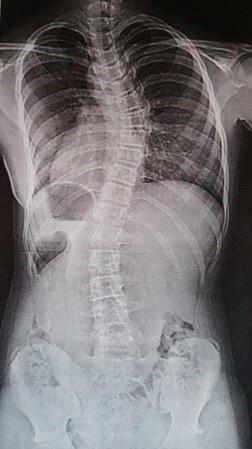

Снимка. 1

Идиопатична сколиоза –рентгенова снимка

на Катерина Шрот – клинични (фото) и рентгенови снимки